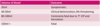

what are the outcomes for different volumes of blood lost due to bleeding over the brain?